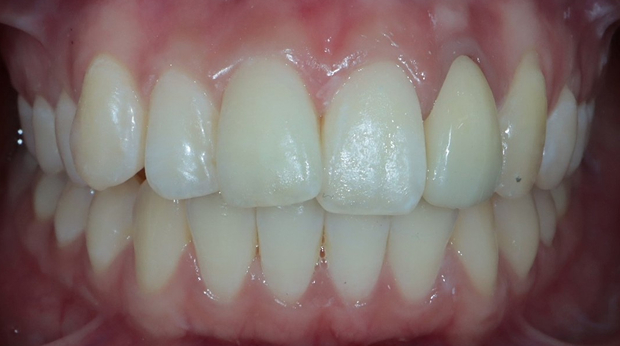

라미네이트